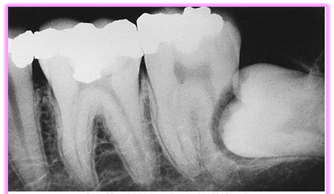

Då visdomständerna är de sista tänderna i bettet att eruptera är förekomsten av total eller partiell retention av visdomständer relativt vanligt. 72% av svenskarna i åldrarna 20 till 30 år har minst en retinerad visdomstand. De kan orsaka smärta, svullnad och infektion – och kan förstöra angränsande tänder och ben. Operativt avlägsnande av visdomständer är ett av de vanligaste kirurgiska ingreppen inom tandvården. Preoperativ bedömning av kirurgiska svårigheter är grundläggande för planeringen inför operativt avlägsnande av retinerade visdomständer. Vinsten av operationen ska alltid överstiga risken med ingreppet. Bedömningen är inte bara viktig för beslut om patienten ska remitteras till specialist eller inte, utan också för att informera patienten om eventuella risker och komplikationer i samband med det operativa ingreppet.

- Karies

- Parodontal sjukdom med ficka > 5 mm distalt på 7:an

Det finns idag inget vetenskapligt stöd för profylaktisk borttagning av asymtomatiska, sjukdomsfria visdomständer. Dock kan extraktion av den asymtomatiska tanden vara fördelaktigt om karies finns i den intilliggande andra molaren, eller om parodontala fickor finns distalt om den andra molaren.